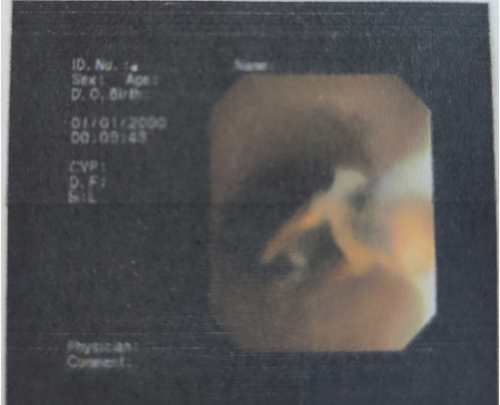

全科医学科主任、主任医师肖智权接诊后仔细查看了王瑛的病历资料,完善肺部CT后显示其右下肺大片状阴影,建议该患者做纤维支气管镜检查。检查过程中,发现患者右肺下叶基底支有异物嵌顿,异物周围因滞留时间长已出现肉芽增生及大量脓性分泌物。内镜医师凭借经验和技术,操作纤维支气管镜的活检钳,将嵌顿的异物从患者右肺下叶基底支处完整取出,医生发现取出的异物竟然是一段辣椒尖。